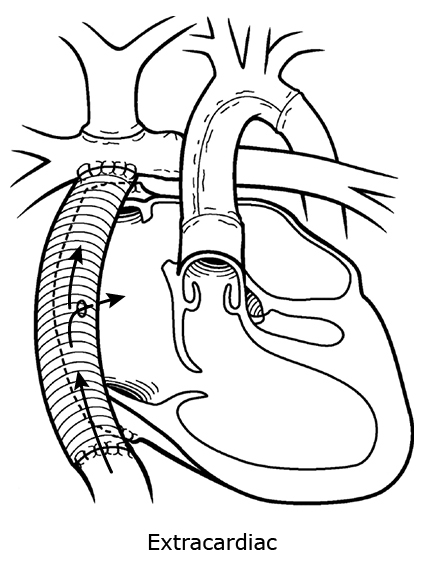

- 3rd stage at 2-3 years

- Fontan procedure

- Direct anastomosis of pulmonary arteries to right atrium

Fontan Procedure for tricuspid atresia https://en.wikipedia.org/wiki/Fontan_procedure